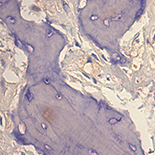

We selected surgically resected osteosarcoma specimens from 116 patients of Zhongnan Hospital of Wuhan University and Hubei Cancer Hospital, Hubei, China, between January 2000 and January 2010 with detailed follow-up data. Twenty osteochondroma specimens from the corresponding period were used as controls. Expression of Src and p-Src was detected in osteosarcoma and osteochondroma by immunohistochemistry. We analyzed the relationship of the 2 proteins and osteosarcoma patient prognosis.

The expression of Src and p-Src in osteosarcoma was significantly higher than the expression level in osteochondroma (P<0.05). The expression levels of the 2 proteins, clinical stage, and tumor metastasis were significantly associated with survival time (P<0.05), but there was no correlation between age or sex and survival time. The expression of Src and p-Src in osteosarcoma was positively correlated.